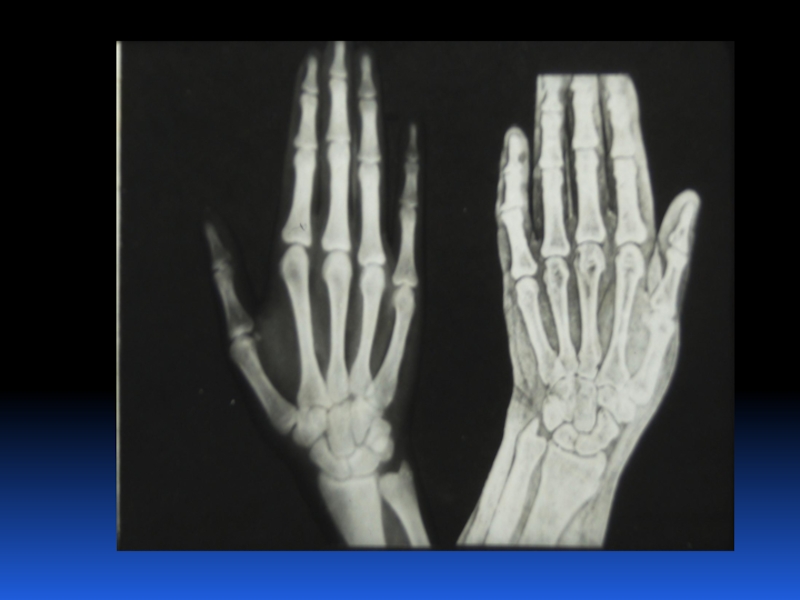

Остеопороз – это системное заболевание скелета, характеризующееся снижением костной массы и нарушением микроархитектоники костной ткани, с последующим увеличением хрупкости костей, со склонностью к патологическим переломам.

Слайд 2 Остеопороз – это системное заболевание скелета, характеризующееся снижением костной

массы и нарушением микроархитектоники костной ткани, с последующим увеличением хрупкости

костей, со склонностью к патологическим переломам.